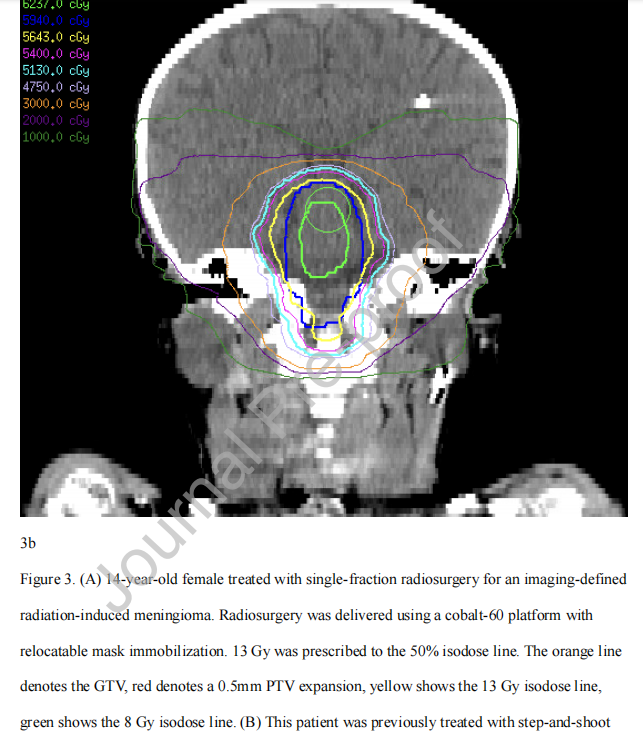

图3 (A) 14岁女性,影像学明确放射诱导脑膜瘤,接受单次放射手外科治疗。放射外科使用钴-60平台和可重新定位的面罩固定。按50%等剂量线照射13 Gy。橙色线为GTV,红色线为0.5mm PTV外扩,黄色线为13 Gy等剂量线,绿色线为8 Gy等剂量线。(B)该患者在放射外科治疗前11年曾因第四脑室复发性脉络膜丛乳头状瘤(33次59.4 Gy)分次照射IMRT治疗。辐射诱发的脑膜瘤区域受照在10-20 Gy之间。

没有已知的儿科数据评估在面罩治疗的情况下,SRS治疗的GTV到计划靶体积(PTV)的适当扩大。成人数据的外推是合理的,目的是使用较小的边际以尽量减少脱靶剂量。例如,成人数据表明,在具有实时高清运动管理(HDMM)系统的钴-60放射外科平台中,PTV为1mm(径向)和1.5 mm(上下)外扩是合适的。其他机构使用更小、均匀的1mm PTV边缘外扩,而额外的数据表明几何0.5 mm PTV外扩可能足以维持肿瘤覆盖。在缺乏儿科特异性数据的情况下,在接受清醒SRS治疗的儿童中,仔细的图像引导、严密的HDMM设置和使用尽可能小的PTV (0.5 mm外扩)是合理的(图3),这取决于当地设备的可用性和机构治疗方案。